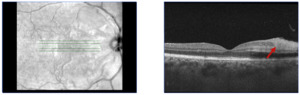

On outpatient follow up one week later, the patient was assessed by a retina specialist where she reported improvement of her visual symptoms. Her visual acuity was 20/60 on the right and 20/100 on the left. Slit lamp exam was normal OU. Fundoscopic exam revealed bilateral peripapillary and posterior pole retinal whitening consistent with Purtscher flecken along with scant inferior intraretinal hemorrhages. Ocular coherence tomography (OCT) showed inner retinal hyperreflectivity / thickening in the nasal macula and focal scant subfoveal subretinal fluid, with the left eye being more affected than the right (Figures 1 and 2). These OCT findings were consistent with acute microvascular ischemia. Decision for conservative management was made and no systemic steroids were administered, given the limited evidence of improved visual outcomes with steroid treatment, as well as the potential ocular side effects of steroid treatment including cataracts, glaucoma and ocular hypertension.8

The patient was subsequently followed up every 2-3 months with repeat dilated exams and OCT. She reported gradual improvement of her visual symptoms. Fundoscopic exam at 5 and 8 months after discharge revealed complete resolution of all the retinal spots, while repeat OCT demonstrated inner retinal thickening consistent with chronic retinal injury. The patient was advised that she could expect further visual improvement over the next several months, but there would likely be some permanent visual deficit.